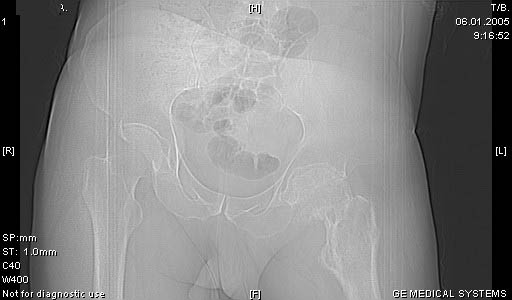

И снова вопрос по эндопротезированию: Пациенту 51 год. Болен с 2000 г, когда отметил умеренные, нараостающие боли в в/3 левого бедра, прогрессирующую контрактуру лев Т/Б сустава.

05.12.04 после падения на бедро боли резко усилились, нога стала неопорной. На рентгенограмме обнаружен патологический перелом шейки бедренной кости. Обследован в отделении костной онкологии. Результат биопсии: асептический некроз проксимального отдела бедренной кости. Вопрос: выбор технологии эндопротезирования - цементная или бесцементная версия. Заранее благодарю! С уважением,А.В.Владзимирский

Учитывая приличную форму вертлужной впадины и возраст

Про ножку трудно сказать, снимки очень короткие.

Проксимальный отдел бедра не виден достаточно на представленных рентгенограммах; но то, что видно, как раз наводит на мысли о цементной фиксации - цилиндрический канал, измененный calcar, кистозные изменения в области большого вертела и т.д.

Soglasen s Евгений И Чекашкин, proximal Femur does not look right. Sarcoma? Pagets, Osteomyelitis?. Technicality of the implantaion will be dependent upon underlying pathology, and the surgeon's level of comfort.

Ацетабулум как-то странно выглядит, с дыркой.

Действительно, проксимальный отдел бедра выглядит подозрительно. По-моему напоминает болезнь Педжета. Кстати, гистологическое заключение в таком случае часто звучит как "хроническое воспаление", "асептический некроз с элементами лейкоцитарной инфильтрации" и т.п. Далеко не все патоморфологи имеют достаточный опыт для дифференцировки костной патологии.